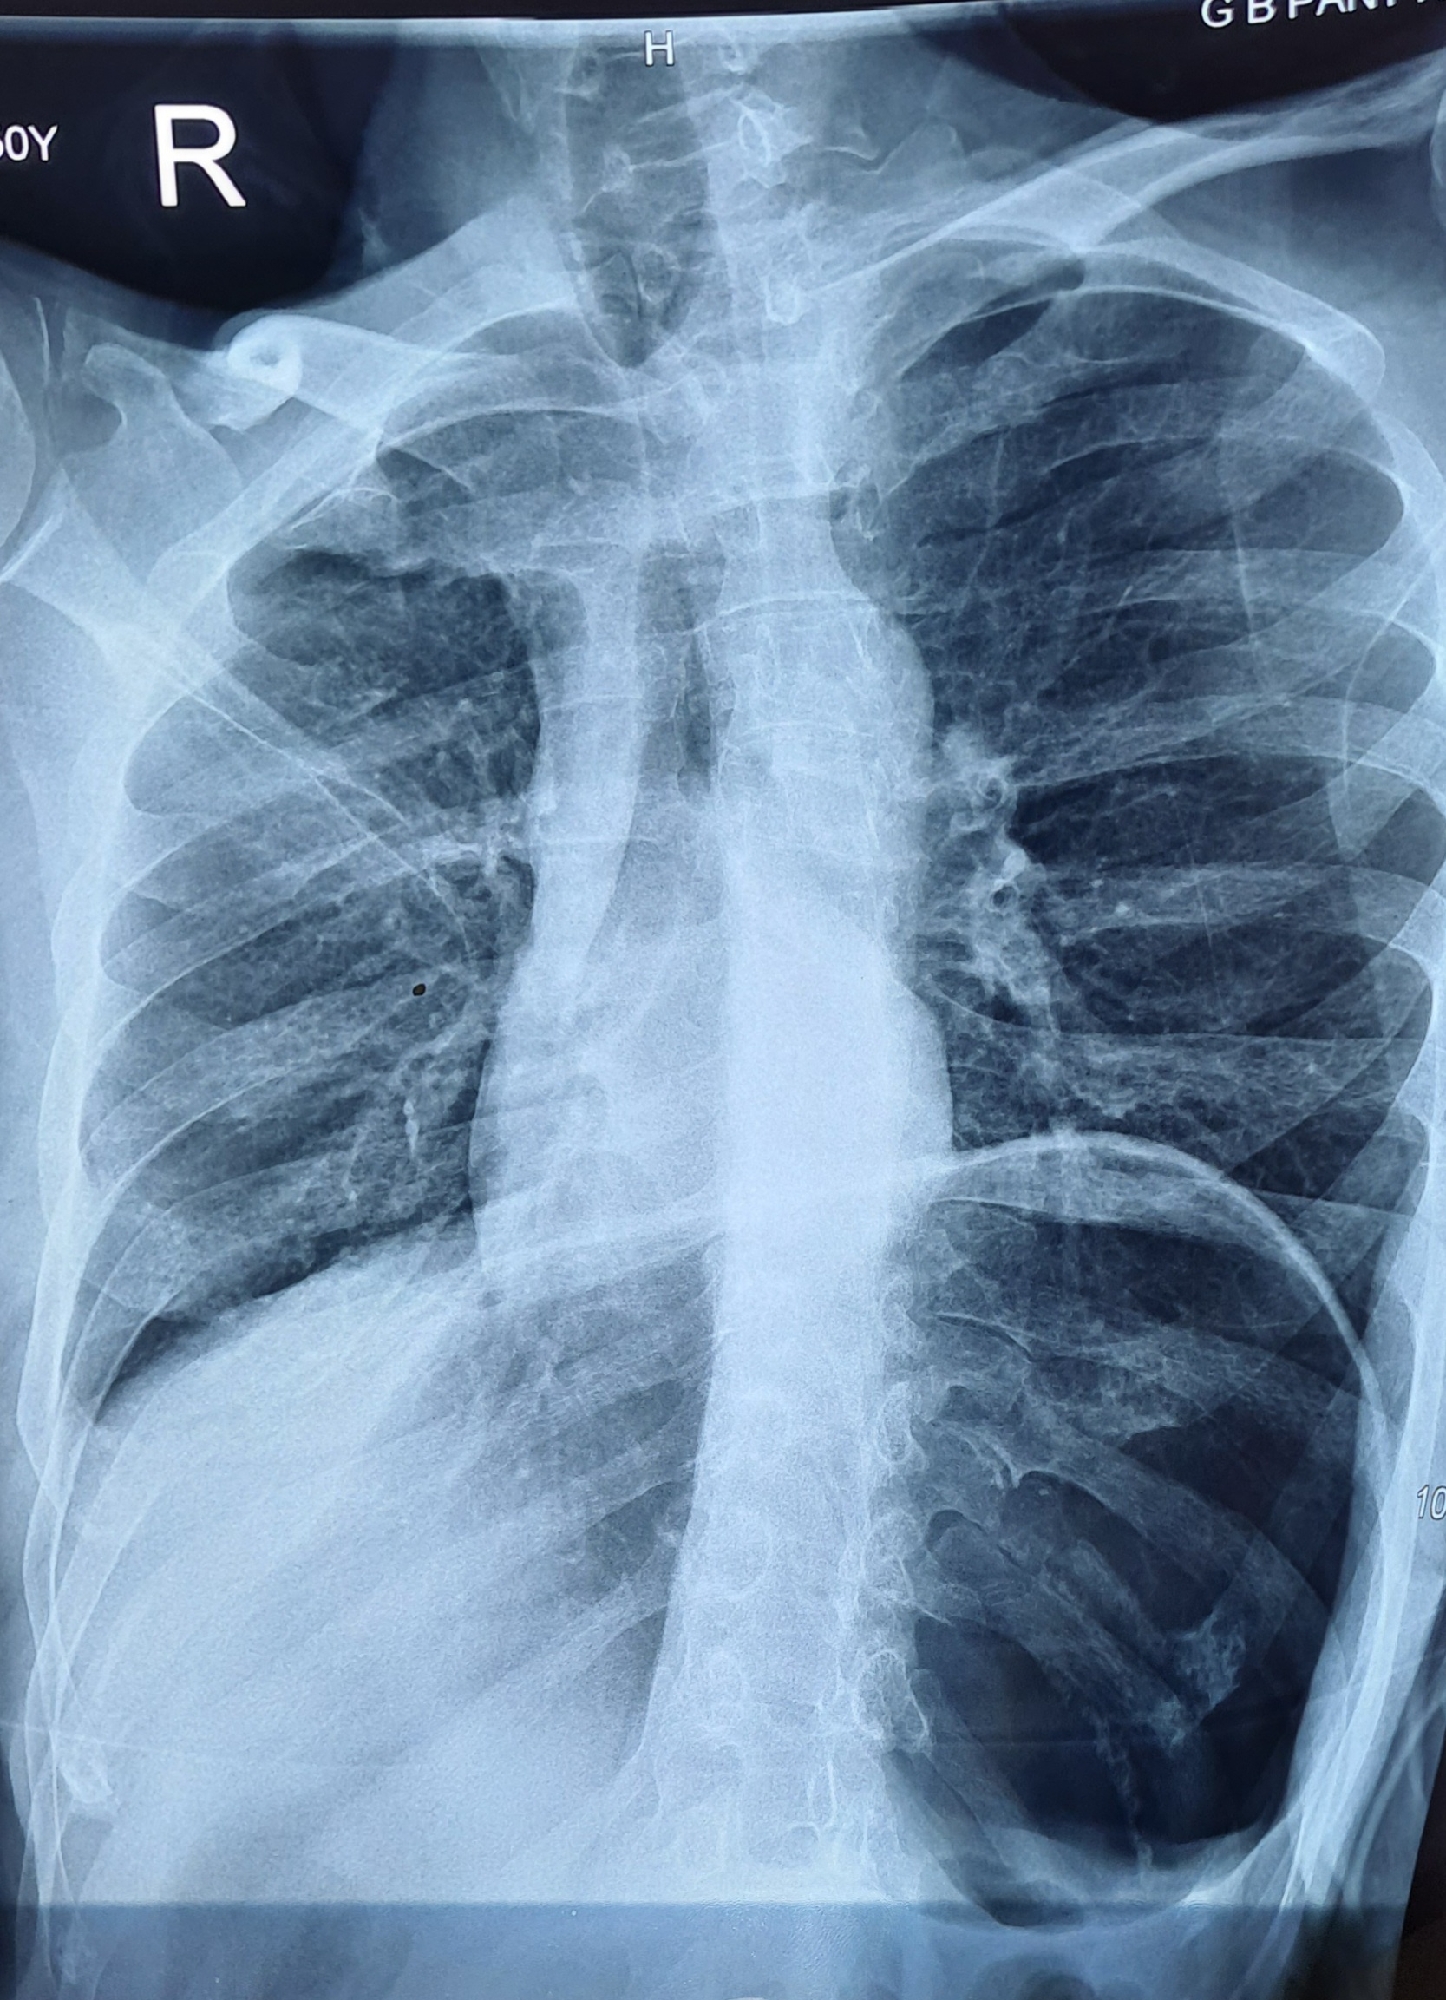

Chest Xray fi lm showing the collapsed lung Download Scientific Diagram